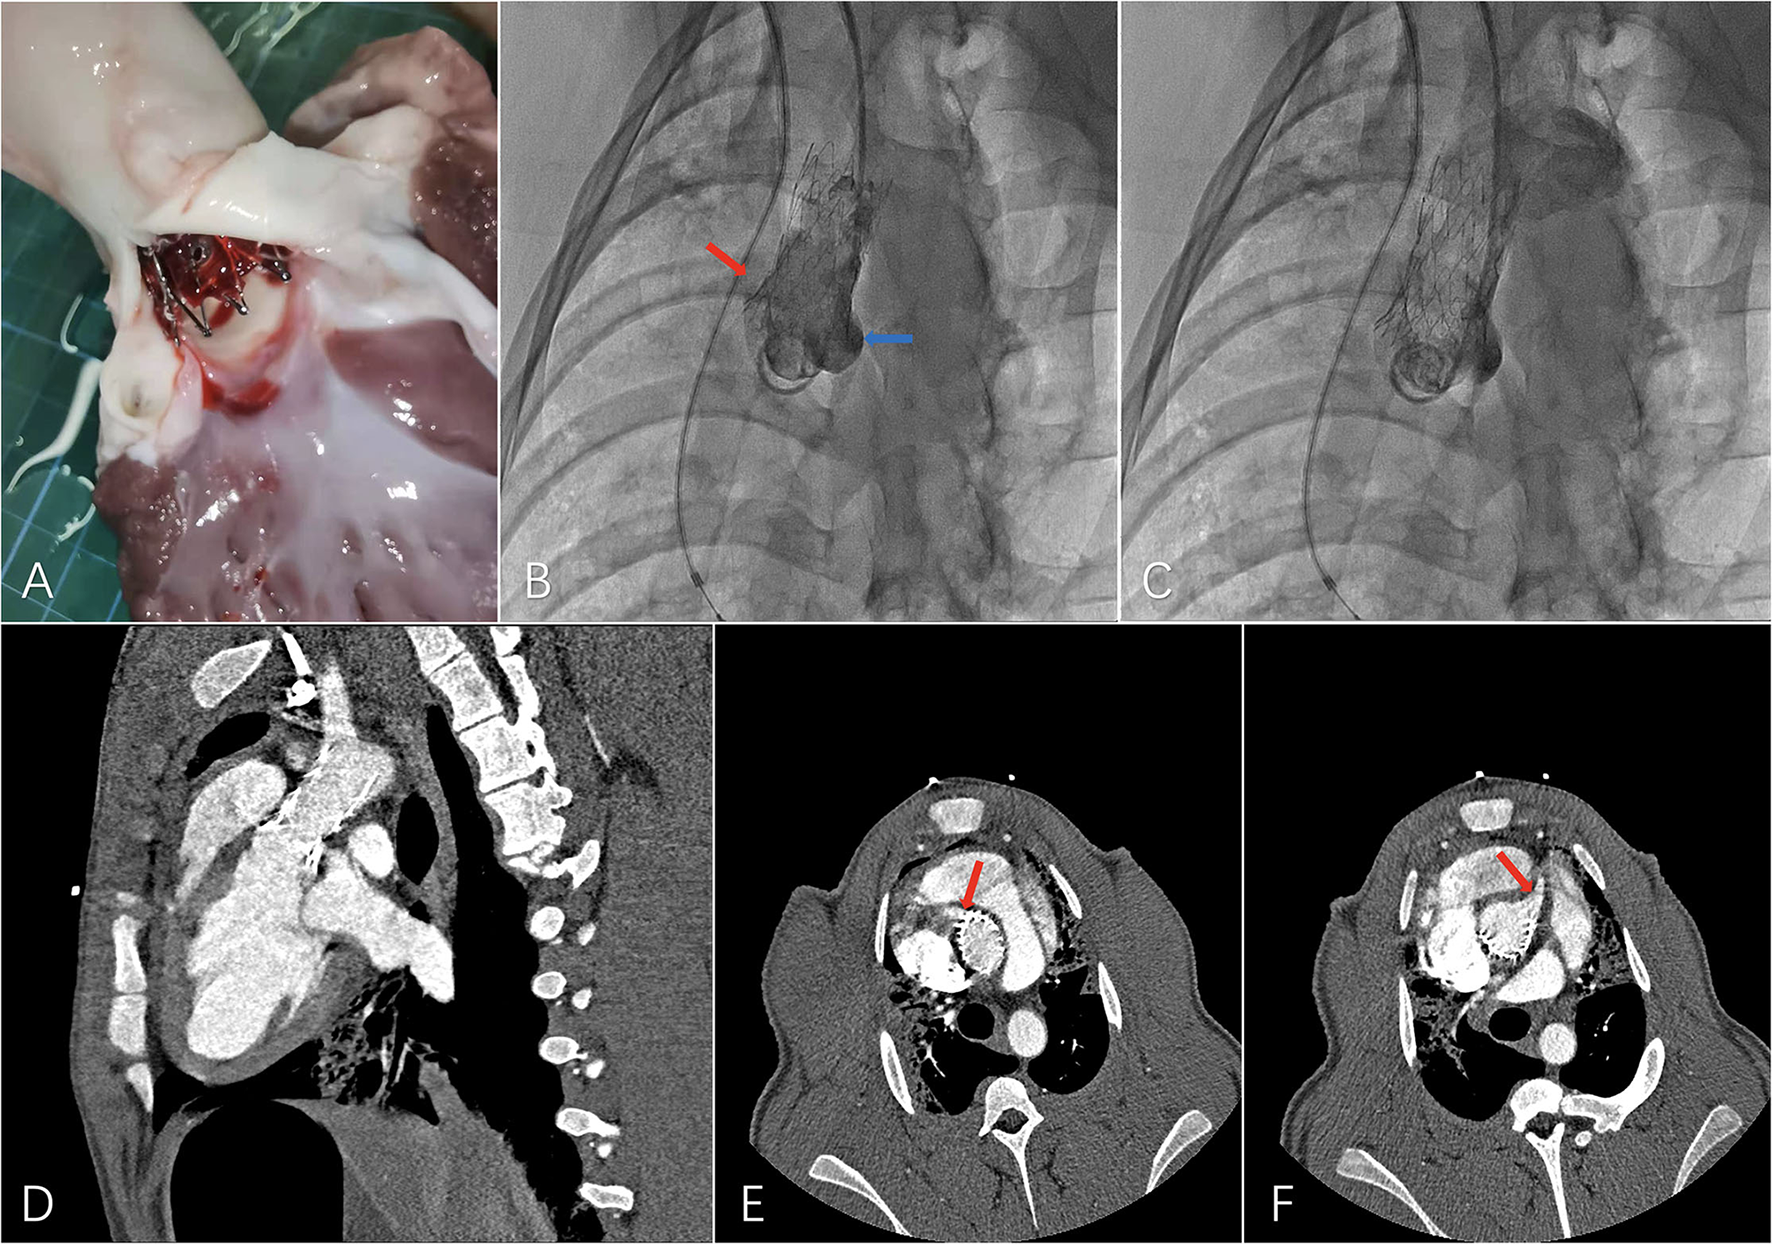

A major challenge for extending the proximal landing zone is to maintain sufficient blood flow of coronary ostia on both sides. To avoid ischemia of the myocardium, the bare metal stent part was set between the distal edge of the higher coronary ostium and the STJ, with the junction of the covered part and the bare metal part positioned in the STJ. A preliminary experiment with the ascending aortic endograft was performed on a swine model with healthy aorta. Although the proximal part of the bare metal exceeded the proximal edge of the higher coronary ostium on the greater curvature side, coronary ostia on both sides showed sufficient blood supply in the final angiography after deployment of the ascending aortic endograft. No adverse events such as stent-graft collapse and migration were observed during the 1-month follow-up, and CTA examination after 1 month showed patent coronary ostia on both sides, suggesting the possibility and safety of extending the proximal landing zone into that region. In future preoperative designs, not only for swine models but also for patients, difference in length between the greater and lesser curvature sides should be considered and measured in detail to ensure accurate positioning of the bare metal part in the region between the distal edge of the higher coronary ostium and the STJ to avoid influencing the blood flow of the coronary ostium on each side (Figure 4).

Figure 4

Preliminary experiment with the novel ascending aortic endograft technique on a swine model. (A) Dissection after a 1-month period follow-up, (B) final angiography showing patent left (blue arrow) and right (red arrow) coronary ostia, (C) final angiography showing patent supra-aortic trunks, (D) computed tomography angiography (CTA) 1 month after the operation with, (E) patent right coronary ostium (red arrow), and (F) patent left coronary ostium (red arrow).